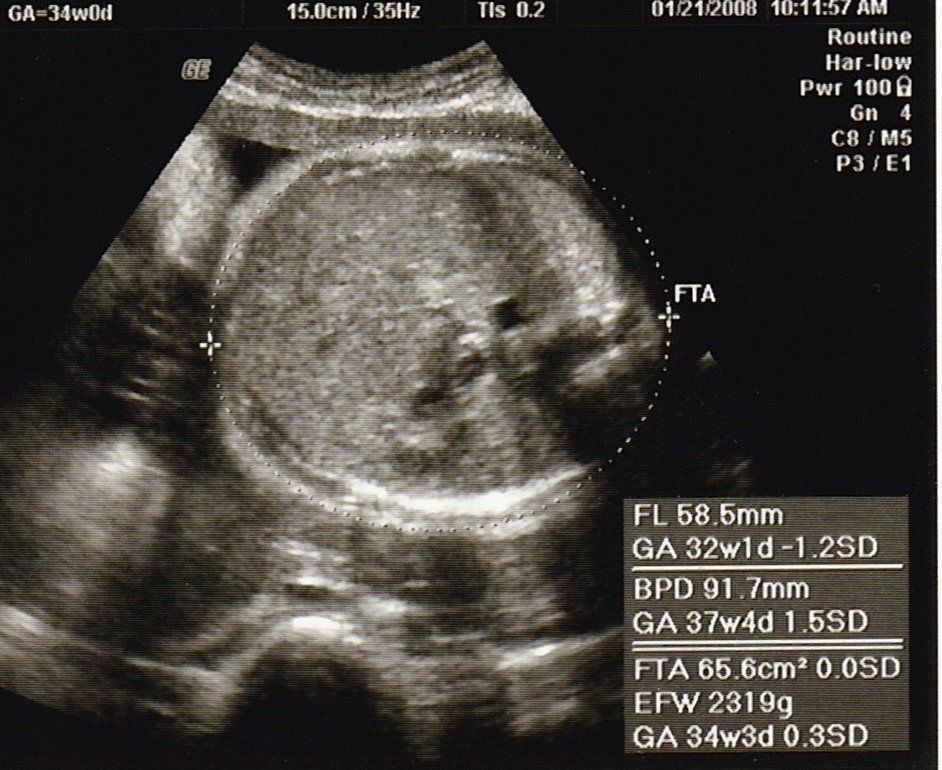

妊娠34週目のエコー写真

最後の血液検査があり、「妊娠37週を超えると正期産に入りますよ」と聞き、「妊婦生活も終わりに近づいているのだな」と感じた検診でした。「今のうちにやりたいことを」と思いましたが、結局、雑誌や本を読むくらいしかできなかったです。美容院に行けなくなるからと、私を含め、髪を切る人が多かった気がします。